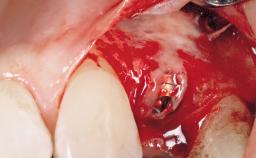

After the placement of three diameter-reduced two-piece implants the bone is augmented with autologous bone chips and DBBM particles to enlarge the crest volume. The surgery is completed with the application of two membrane layers and primary wound closure.

Bone Volume Deficient horizontally, allowing simultaneous augumentation